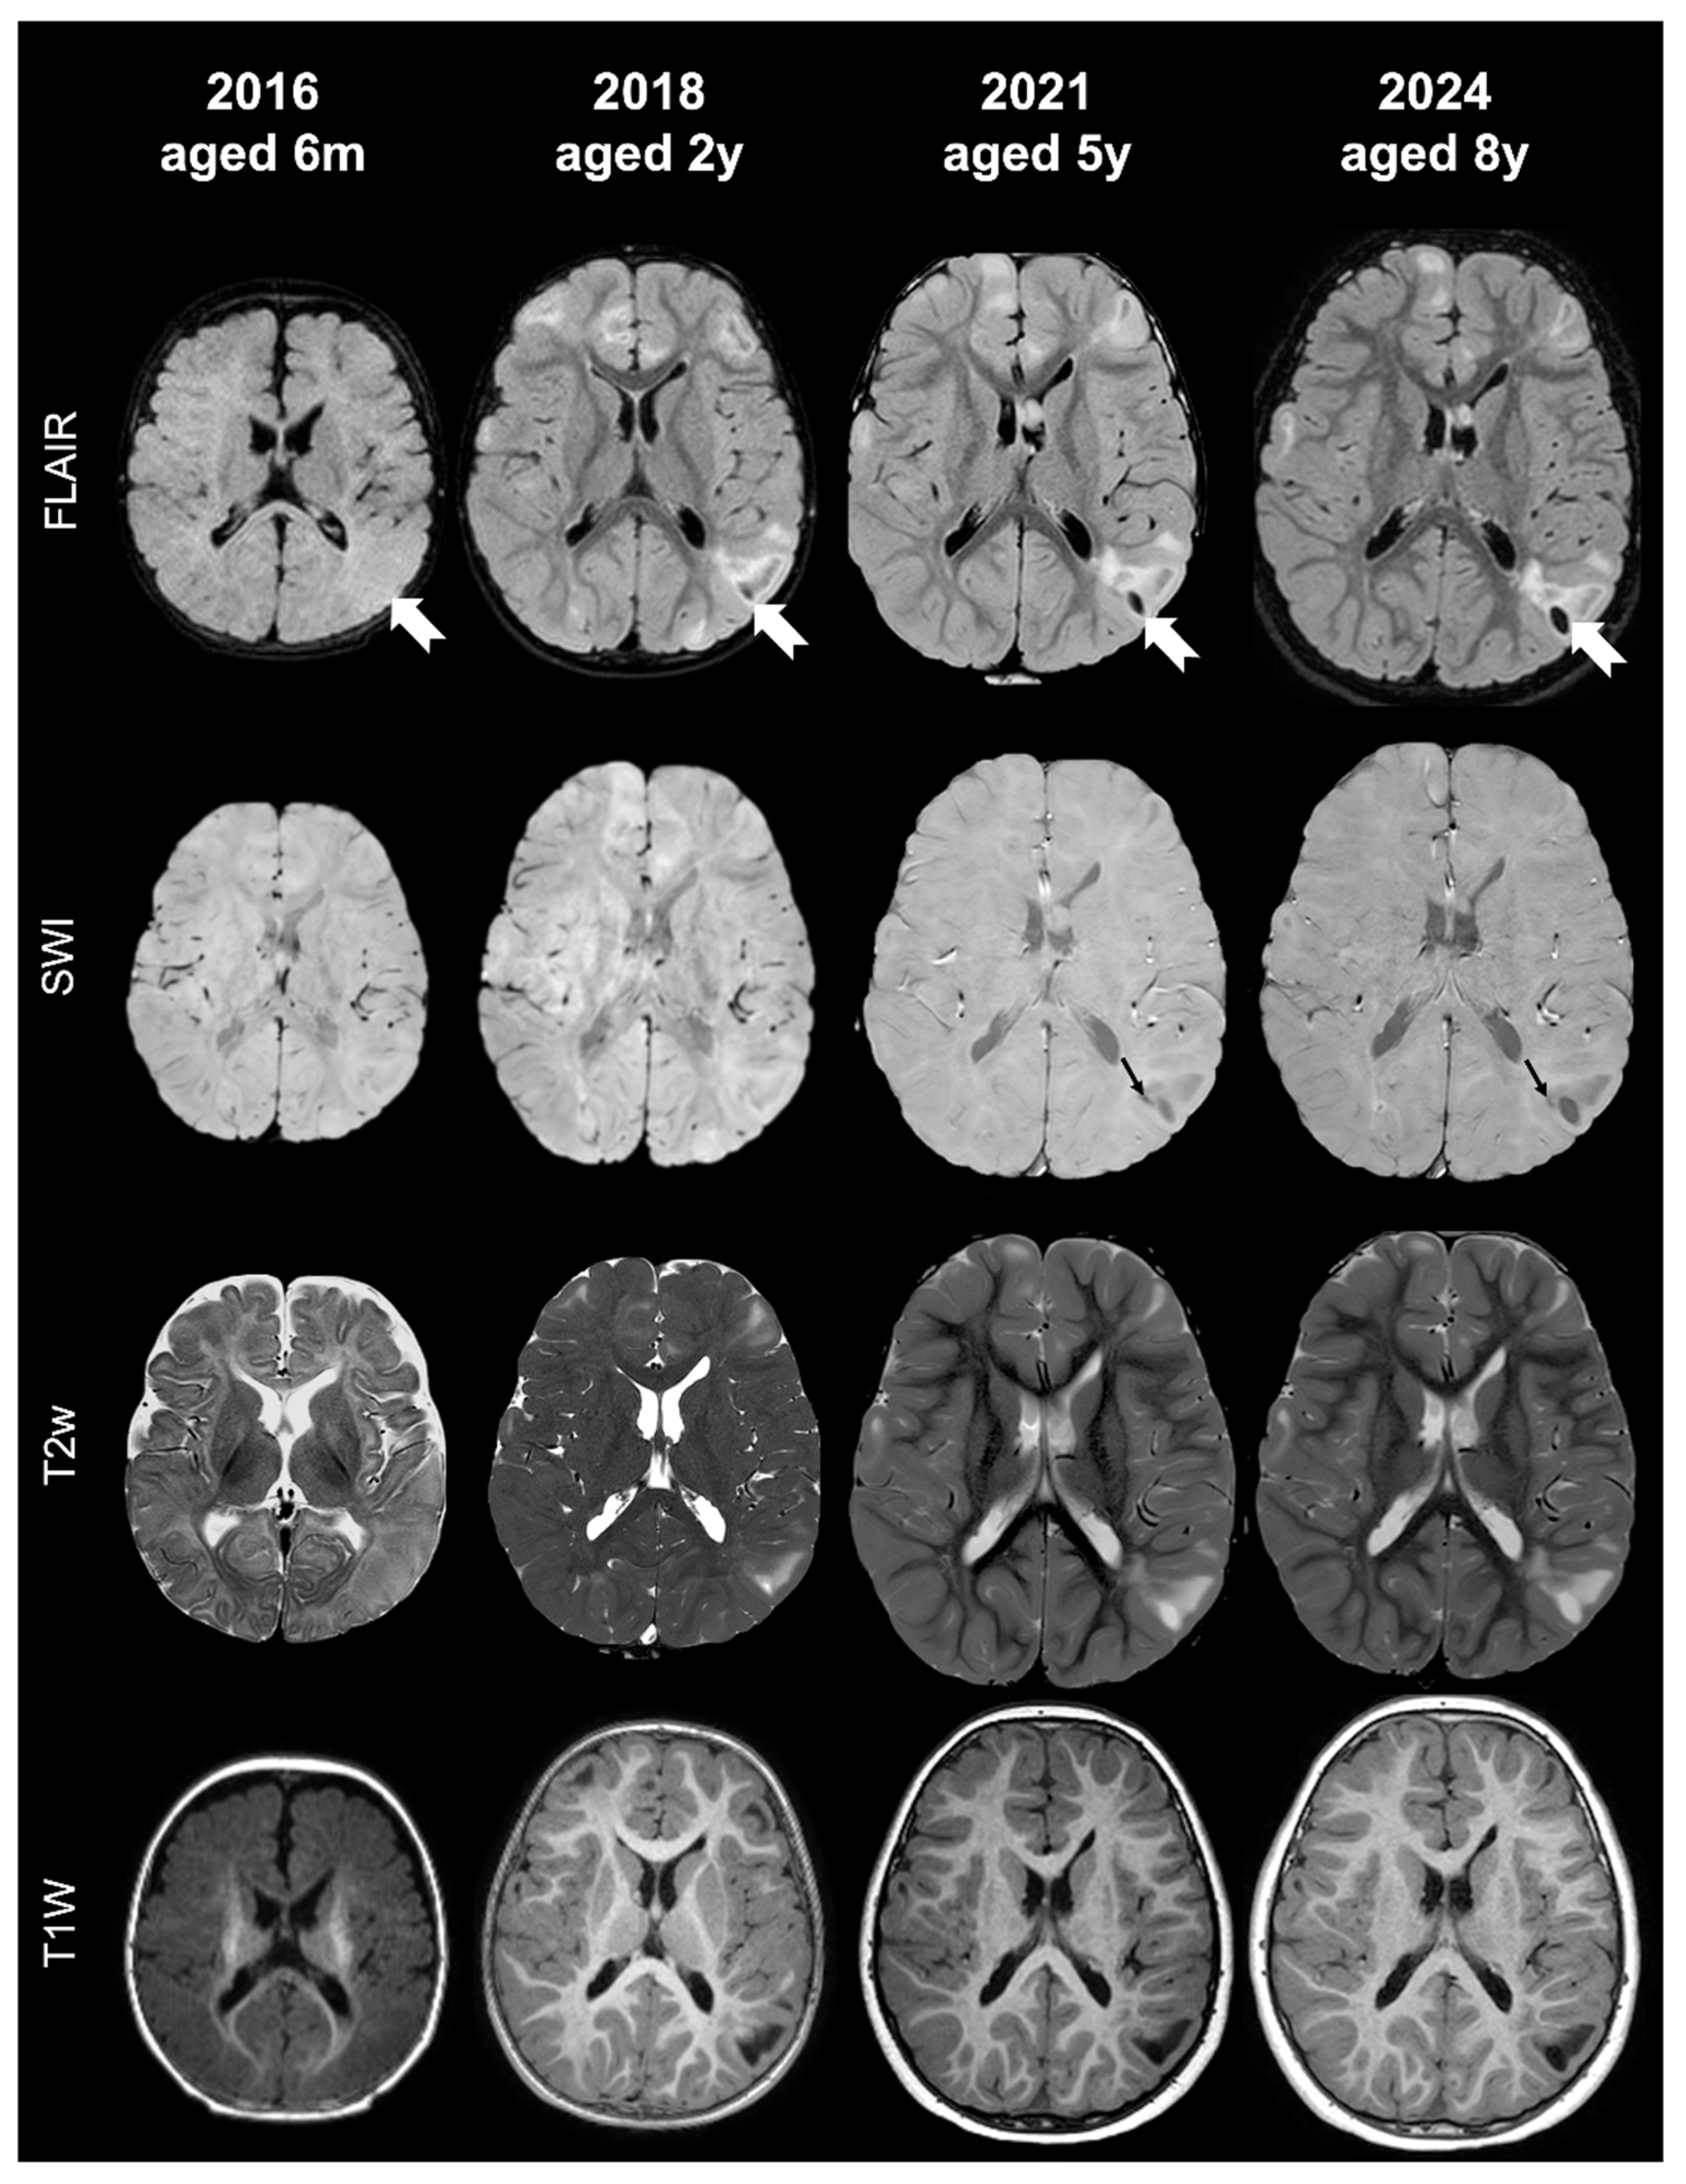

- Tuber C: hypointense on volumetric T1-weighted images and homogeneously hyperintense on T2-weighted images with inner calcifications on SWI, further divided into the following:

- Tuber D: hypointense on volumetric T1-weighted images and homogeneously hyperintense on T2-weighted images with a central cystic area of vacuolization, regardless of the presence of associate calcification(s).

- Tuber C1: with subtle, non-confluent, pinpoint-like calcifications on SWI (micro-calcified)

- Tuber C2: with large, confluent, linear or curvilinear calcifications on SWI (macro-calcified)

- Tuber D: hypointense on volumetric T1-weighted images and homogeneously hyperintense on T2-weighted images, with a central cystic area of vacuolization, regardless of associated calcification(s).

- Russo, C.; Coluccino, S.; De Leva, M.F.; Graziano, S.; Russo, C.; Mazio, F.; De Liso, M.; Cicala, D.; Nastro, A.; Palladino, F.; et al. Cortical Tubers’ Transformation in Pediatric Patients Diagnosed with Tuberous Sclerosis Complex: A Retrospective Longitudinal MRI Analysis. J. Clin. Med. 2025, 14, 7665. [Google Scholar] [CrossRef]